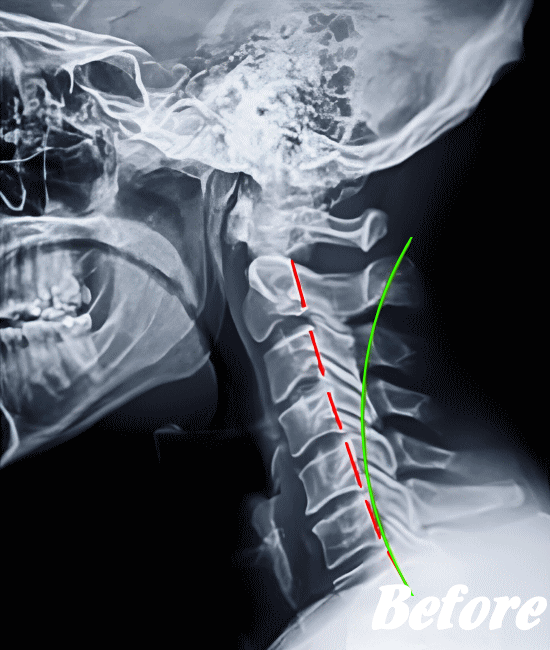

HALOカイロプラクティック☆平和島整体院では、骨盤(仙腸関節)から背骨(腰椎、胸椎、頸椎)、肋骨(肋椎関節)、肩甲骨(肩甲胸郭関節)などを調整し緩めることで、首(頚椎)にかかる負担を取り除き、可動域を良くして痛みを解消していきます。

首や肩周りの症状では、肩甲胸郭関節(肩甲骨周辺)を調整することは必須です。